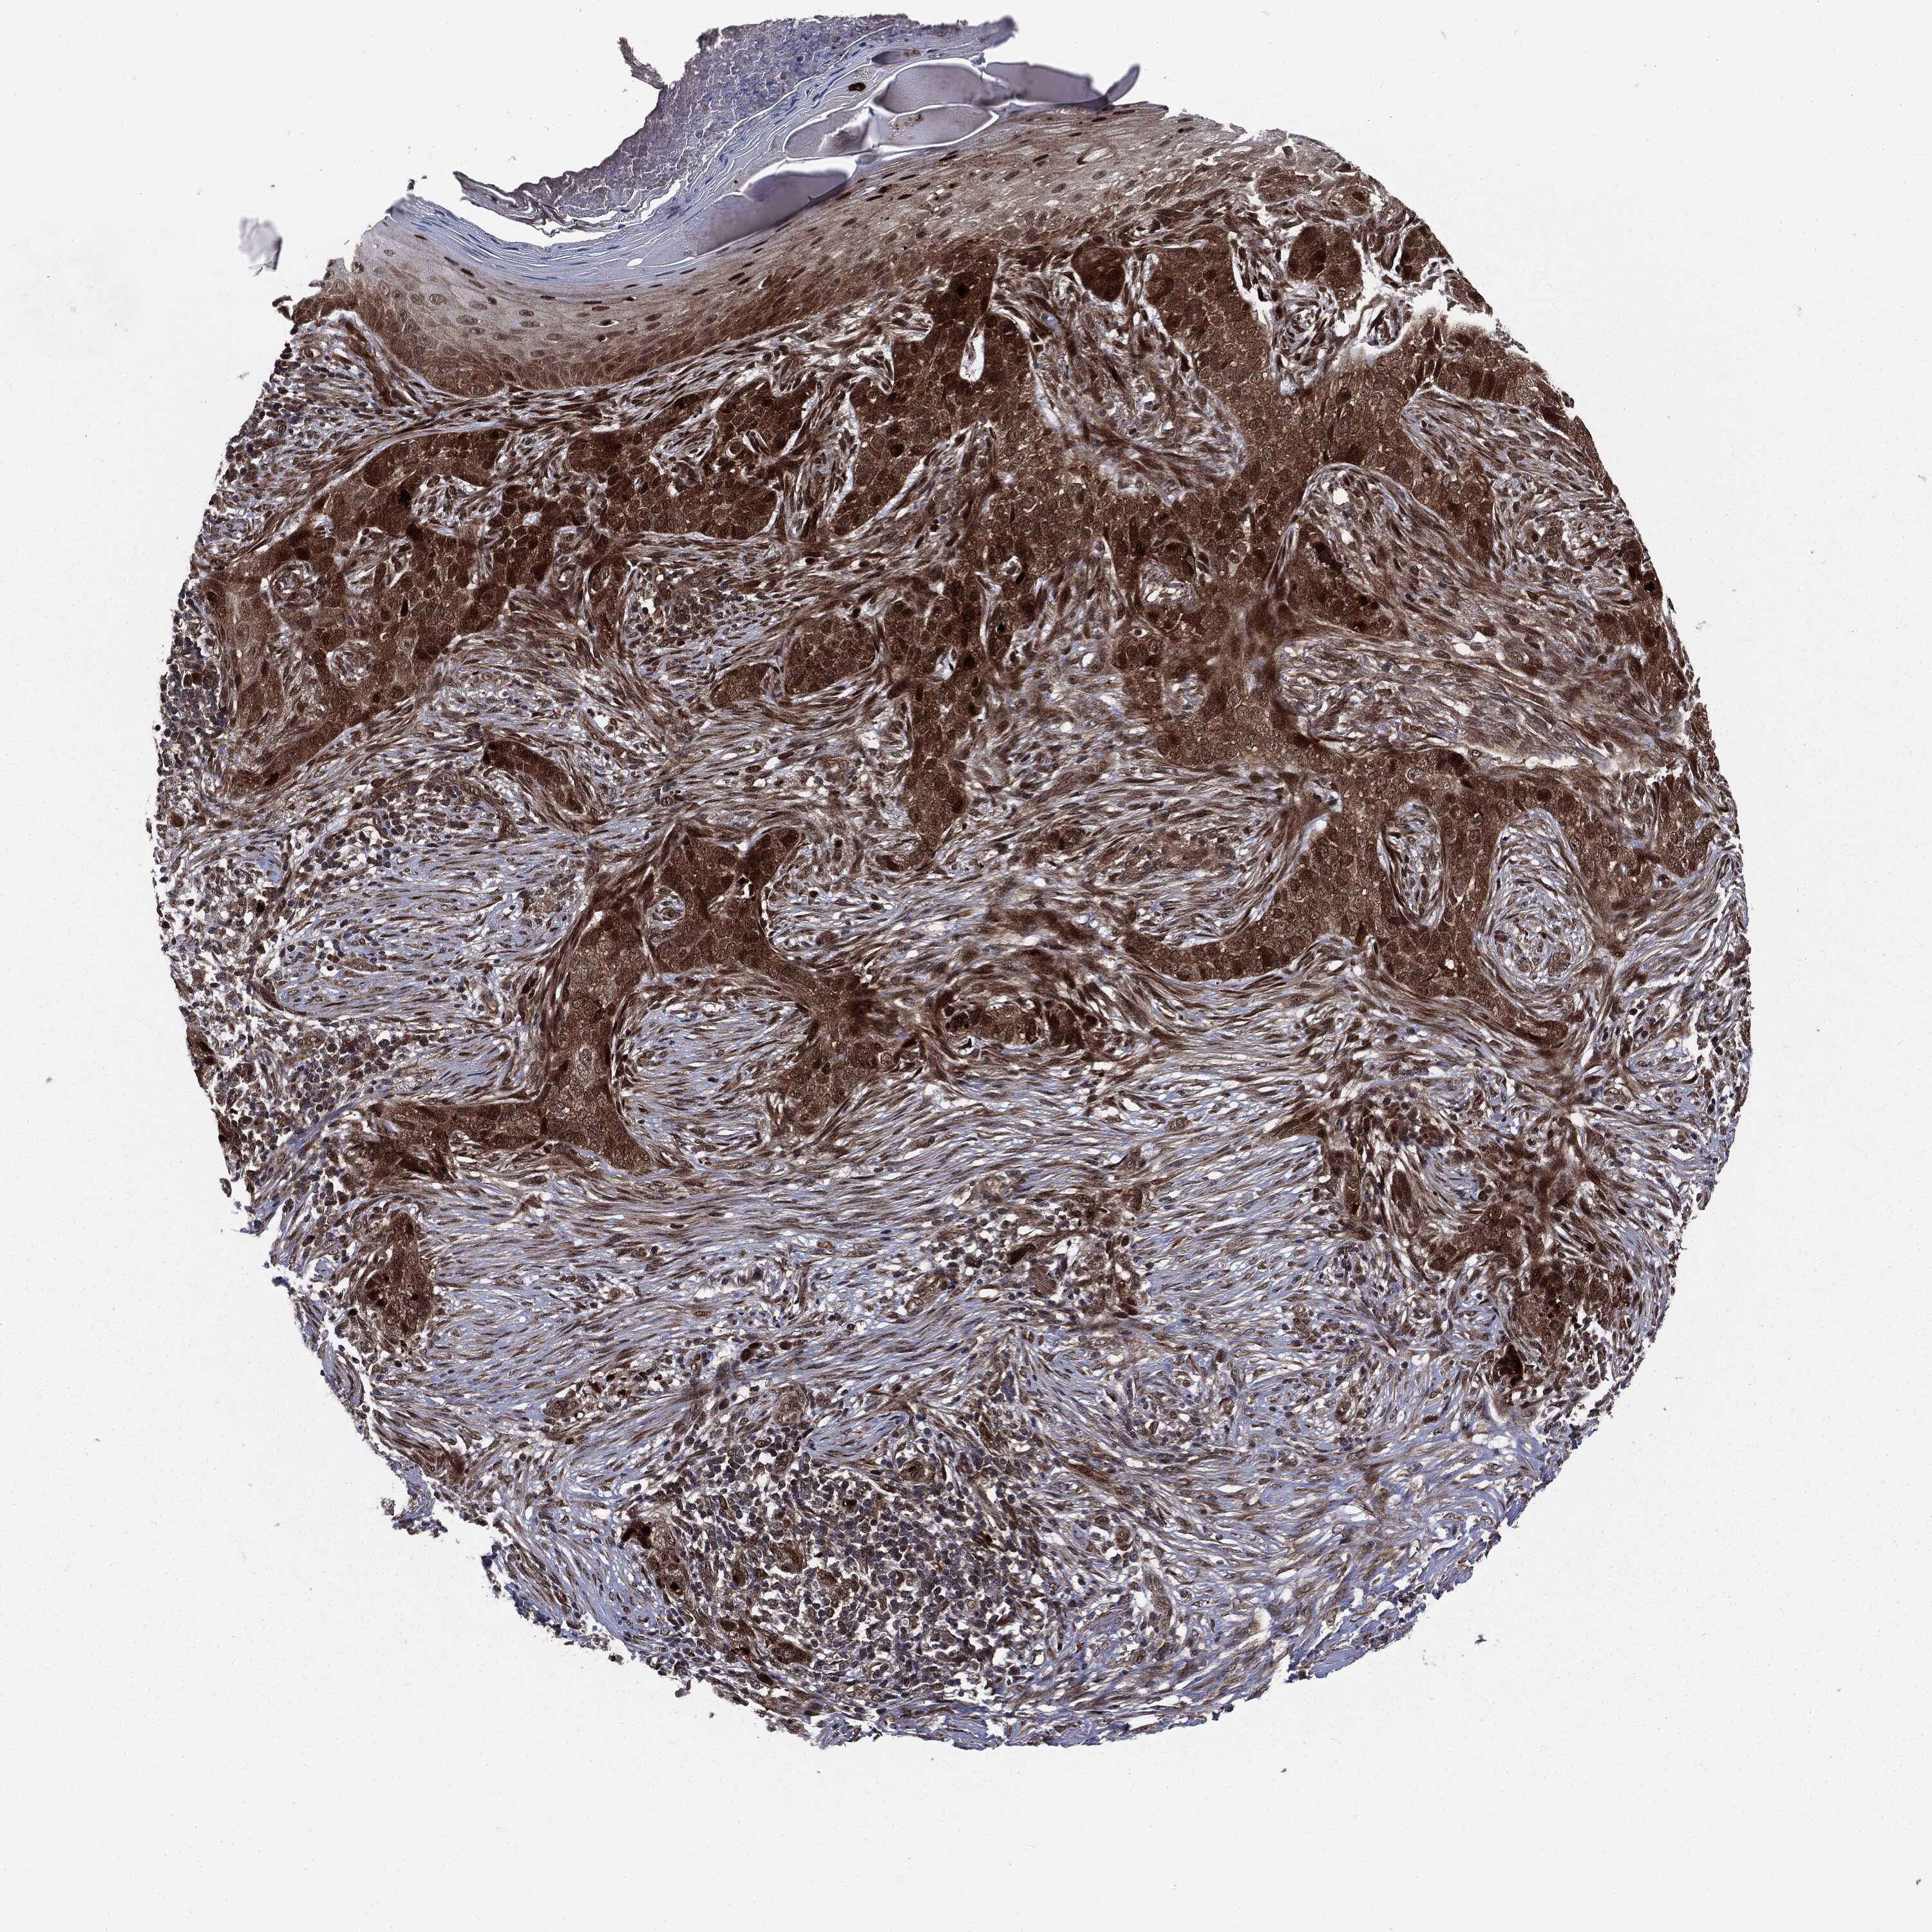

Basal cell and squamous cell cancer

SKIN CANCER - Protein expressioni

A mouse-over function shows sample information and annotation data. Click on an image to view it in a full screen mode. Samples can be filtered based on level of antibody staining by selecting one or several of the following categories: high, medium, low and not detected. The assay and annotation is described here.

Antibody stainingi

Antibody staining in the annotated cell types in the current human tissue is reported as not detected, low, medium, or high, based on conventional immunohistochemistry profiling in selected tissues. This score is based on the combination of the staining intensity and fraction of stained cells.

Each image is clickable and will lead to virtual microscopy that enables deeper exploration of all samples and also displays staining intensity scores, fraction scores and subcellular localization as well as patient and tissue information for each sample.

Antibody CAB080136

Staining

High

Medium

Low

Not detected

Intensity

Strong

Moderate

Weak

Negative

Quantity

>75%

75%-25%

<25%

None

Location

Nuclear

Cytoplasmic/membranous

Cytoplasmic/membranous,nuclear

Squamous cell carcinoma in situ, NOS

Squamous cell carcinoma, NOS

Squamous cell carcinoma, metastatic, NOS

Basal cell carcinoma